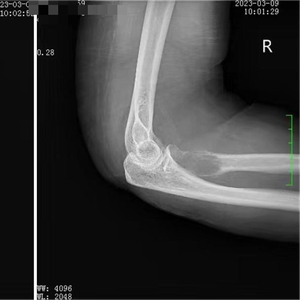

术前影像资料

右尺骨近端团块状异常信号影(—范围约21mm×34mm)